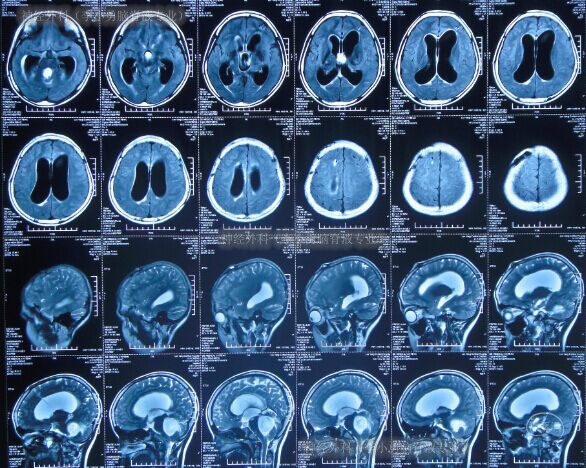

第1次分流管调整术1年5个月后即2013年8月19日(患儿11岁时),再次出现呕吐、腹部膨隆;于是当天就诊(第3次)于河南省洛阳市某医院,查CT显示第四脑室及侧脑室均显著再扩大(图-5);且腹部CT再示分流管周围出现包裹性积液(片子遗失)。给予经分流管泵抽吸脑脊液进行细菌培养,并给予抗炎、脱水等处理。

图-5:2013年8月19日头颅CT

术后好转出院,出院时头颅CT示脑室显著缩小至基本正常(图-8)。

图-8:2013年12月31日头颅CT

2014年6月14日,患儿第7次就诊于河南省洛阳市某医院,复查头颅MRI显示脑室大小在脑脊液外引流条件下尚无显著异常(图-9)。

图-9:2014年6月14日头颅MRI

医生又经分流管泵抽取脑脊液进行培养结果回报为无花果沙雷菌感染。之后静脉抗炎治疗1月后即2014年7月18日,期间体温逐渐恢复至正常,查头颅CT示脑室扩大且又出现了脑室壁增强的“脑室炎”表现(图-10)。

图-10:2014年7月18日头颅MRI